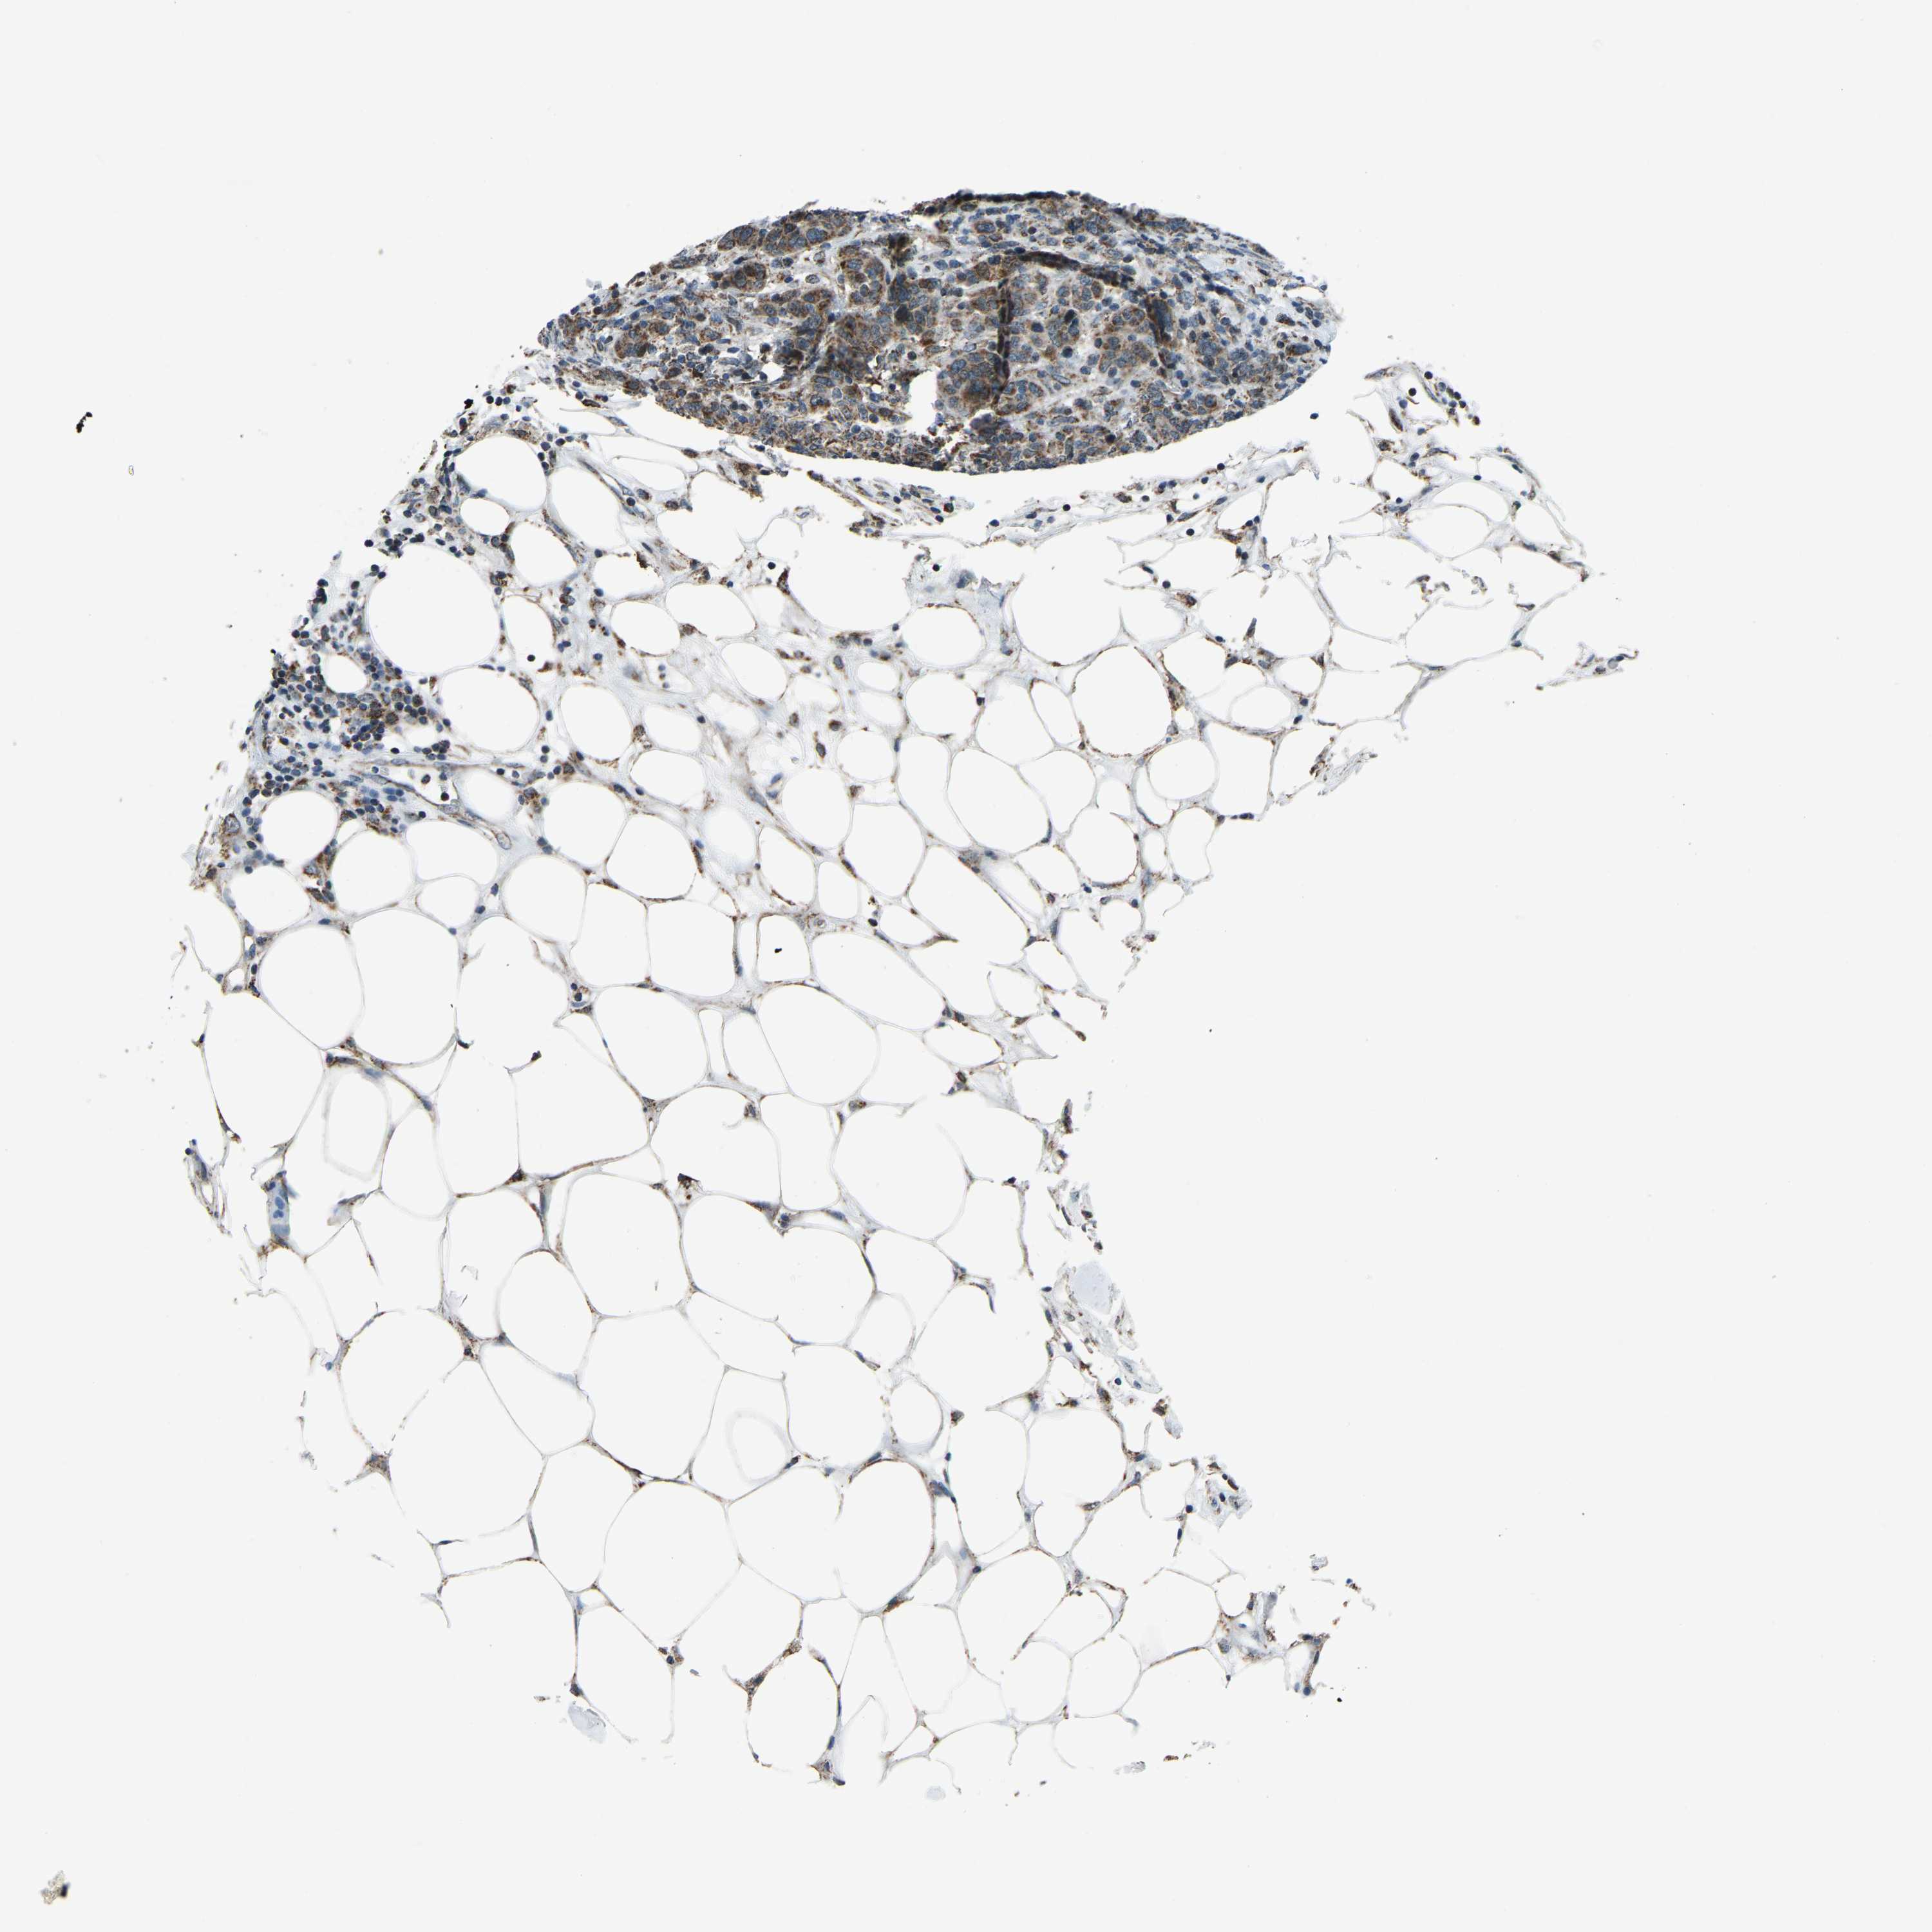

CANCER BREAST CANCER Show tissue menu

BRCA TCGA BRCA VALIDATION PROTEIN EXPRESSION